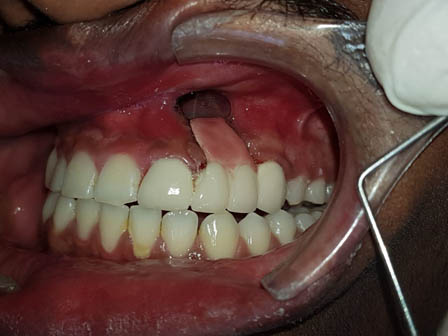

भूल कमीत कमी किंवा अगदी न देऊनही, लेझरच्या साहाय्यानेही विना वेदना ,विना रक्तस्त्रावही हिरडीवरील उपचार करता येतात. तसेच हिरड्यांमधून रक्त , पू,येते असेल,दात ढिले झालेलं असतील तर त्या हिरड्यांवरही योग्य वेळीच योग्य उपचार (फ्लॅप सर्जरी विथ और विदाऊट बोन ग्राफ्टिंग ) करता येते . परंतु दुर्दैवाने हिरड्या खराब झाल्यामुळे किंवा खूप किडल्यामुळे दात काढूनच टाकावा लागला तर त्या जागेवर स्क्रू चे रोपण करून ( इम्प्लांट) पुन्हा पक्का दात बसविता येतो. याच पद्धतीने सर्वच्या सर्व दातही (संपूर्ण कवळीही) बसविता येते. मात्र यासाठी आधुनिक तंत्रज्ञानाची मदत घ्यावी लागत असल्यामुळे या पद्धती थोड्या खर्चिक असतात.

याशिवाय माणसाच्या उत्क्रांती मुळे कमी होणाऱ्या जबड्यांच्या आकारावर दातांची संख्या तेवढीच म्हणजे 32 राहिल्यामुळे सर्वात शेवटी उगवणाऱ्या अक्कलदाढा अडकल्यामुळे ,किंवा तिरक्या उगवल्यामुळे, बहुतांशी रुग्णांना शस्त्रक्रिया (ऑपरेशन) करून काढून टाकाव्या लागतात. अन्यथा या दाढांमुळे, पुढचे सर्व दात वाकडेतिकडे होण्याची किंवा पुढे येण्याची शक्यता असते.

याशिवाय आजकालची प्रमुख समस्या म्हणजे पुढे आलेले दात किंवा दात वाकडेतिकडे असणे, दातांमध्ये फटी असणे की ज्यामुळे तुमचा चेहरा, तुमचं हसणं विद्रूप तर दिसतंच पण त्यामुळे खाताना, गिळताना, बोलतानाही त्रास होतो तो वेगळाच ... यावर दंततव्यगोपचार (ऑर्थोडोंटिक) हे प्रभावी माध्यम (उपचार) आहे. दाताना क्लिप्स लावून असे वाकडे तिकडे दात सरळ रेषेत येतात, पुढे आलेले दात मागे नेता येतात, दातातील फटीही बंद करता येतात. याशिवाय, जास्त वाढलेला जबड्यांची दुरुस्तीही योग्य तऱ्हेने करता येते. वाढीचे वय संपून गेल्यानंतरही, प्रौढांनाही कमी किंवा जास्त वाढलेल्या जबड्यावर शस्त्रक्रिया करून सुंदर चेहरा मिळविता येतो. उपचार चालू असताना अवघडल्यासारखे (awkward) वाटू नये म्हणून विशेषतः प्रौढांना, दातांच्या रंगाच्या, कमीत कमी दिसणाऱ्या क्लिप्स ही उपलब्ध आहेत. याच सोबत अलायनर्स(aligners)म्हणजे अजिबात न दिसणाऱ्या क्लिप्स सुद्धा उपलब्ध आहेत.